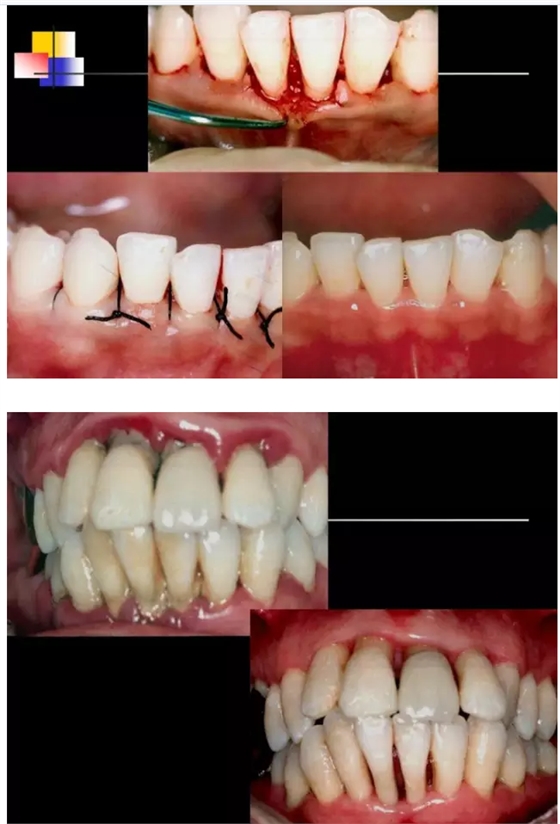

【牙科知識(shí)】牙周病相關(guān)手術(shù)圖解,非醫(yī)學(xué)專業(yè)勿點(diǎn)